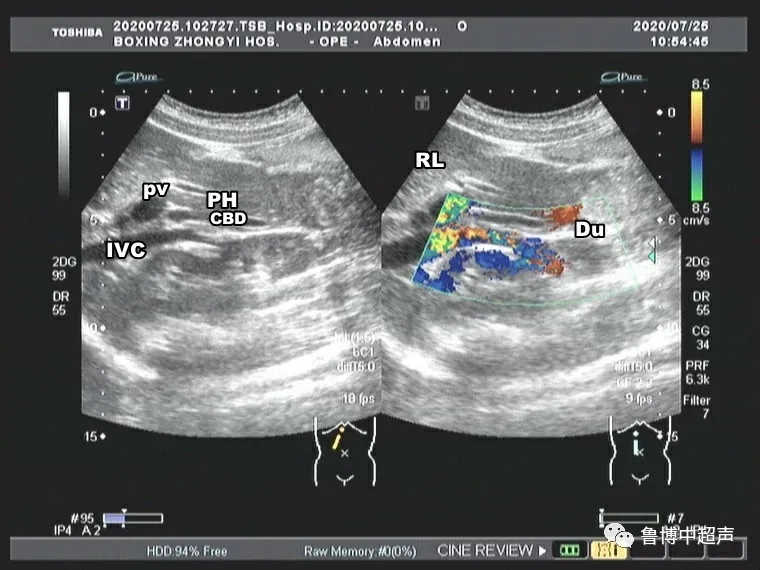

图9 IVC下腔静脉 PV门静脉 CBD胆总管 Du十二指肠

右肋缘下经胰头可显示胆总管下段横切面。